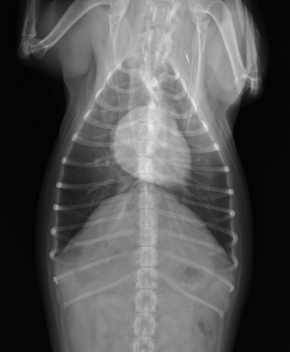

胸部X線検査(心臓の大きさや肺の状態の評価)

■心臓レントゲン 異常